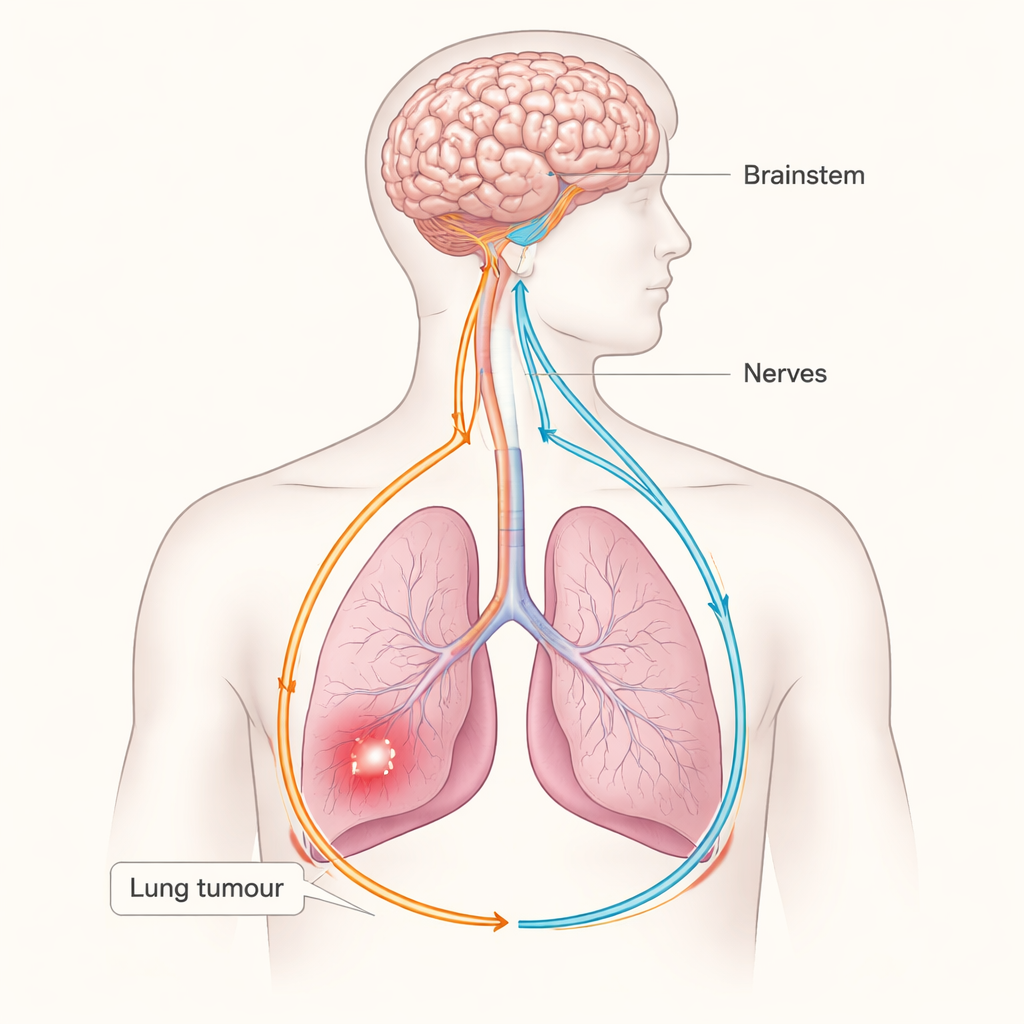

Il cancro è solitamente descritto come una battaglia tra cellule fuori controllo e il sistema immunitario, ma questo studio rivela un terzo protagonista sorprendente: il sistema nervoso. I ricercatori mostrano che i tumori polmonari possono sfruttare un circuito nervoso sensoriale–simpatico che collega i polmoni al cervello e quindi usare quel circuito per indebolire le difese antitumorali naturali dell’organismo. Capire questo «cavo» nascosto tra i tumori e il cervello potrebbe aprire nuove strade per curare il cancro al polmone mirando ai nervi e ai loro segnali, non solo alle cellule tumorali.

Dal tronco encefalico a segnali di tipo stressificato nel polmone

Per capire come questi segnali sensoriali vengono elaborati dal cervello, il team ha tracciato il circuito a monte. I marcatori di attività hanno mostrato che, quando erano presenti tumori polmonari, regioni del tronco encefalico che ricevono input vagali si attivavano, in particolare un’area chiamata medulla ventrolaterale rostrale, un hub chiave che aumenta l’output simpatico di «lotta o fuga». Spegnere i neuroni sensoriali NPY2R/TRPV1 ha attenuato questa attività del tronco encefalico e ridotto il numero di fibre nervose simpatiche e i livelli del messaggero dello stress noradrenalina nell’area tumorale. Anche il silenziamento dello stesso hub del tronco encefalico ha rallentato la crescita tumorale. Complessivamente, questi risultati delineano un circuito chiuso: il tumore stimola i nervi sensoriali vagali, il tronco encefalico risponde aumentando l’efflusso simpatico, e i nervi simpatici ricadono sull’ambiente polmonare in modo favorevole al cancro.